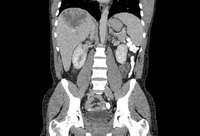

Abscesso hepático: tomografia computadorizada (TC) mostrando um abscesso hepático (7 cm x 5 cm) em um homem de 46 anos de idade que apresentou febre, fadiga e tosse

Do acervo de imagens radiológicas do Massachusetts General Hospital